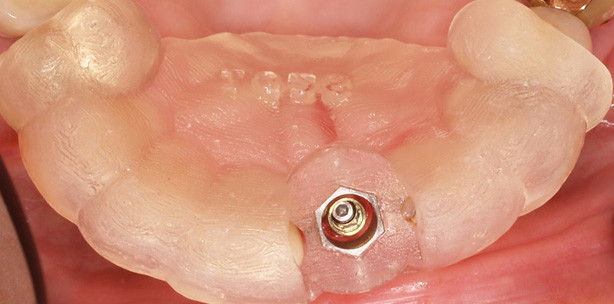

Beispielhaft ist ein Fall mit einer zahngetragenen Schablone dargestellt. Die Expert­Ease-Bohrschablone (Abb. 7) wird über die Zähne fixiert. Dadurch ist eine exakte Position der Navi­gationsschiene hergestellt. Nach der Stanzung durch die Bohrschablone und Exzision des Weichgewebes inklusive des Periosts erfolgt die Pilotbohrung in der geplanten Länge (Abb. 8). Ebenso ist ein Zugang mit einem Mukoperiostlappen möglich, je nach Präparationsform muss dafür eventuell eine Perforation der Bohrschablone erfolgen. Durch die Hülsen wird das Implantatbett in aufsteigender Bohrergröße aufbereitet, dabei wird die Führung der Sleeve-on-Drills über die Hülse sowohl in der Richtung als auch in der Präparationstiefe geführt (Abb. 9).  Bei der Insertion des Implantats (XiVE® S, Ø 3,8mm, Länge 13mm, DENTSPLY Friadent, Mannheim) muss die Oberkante des Einbringinstruments mit der Führungshülse bündig abschließen. Die Markierungspunkte stellen die richtige Ausrichtung der Implantatinnengeometrie sicher (Abb. 10). Nach Entfernung des Einbringinstruments kann die TempBase (Abb. 11) entnommen oder zur provisorischen Versorgung des Implantats benutzt werden. Die postoperative Panoramaschichtaufnahme (zur Verdeutlichung der Implantatschulter mit Verschluss-Schraube) zeigt die exakte Umsetzung der geplanten Implantatposition (Abb. 12). Direkt postoperativ erfolgt die Versorgung mit einem laborgefertigten Provisorium (Abb. 13). Bei Sofortversorgungen von Einzelzahn­implantaten in der Front sollten keine statischen und dynamischen Okklusionskontakte auf dem Provisorium bestehen. Weiche Kost und Schonung des Implantats in den ersten vier Wochen tragen wesentlich zum Erfolg bei. Nach Einheilung und Ausformung der Weichgewebe kann die definitive prothetische Versorgung erfolgen.